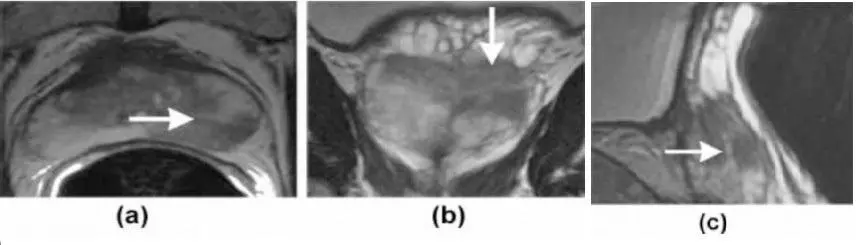

To identify PCa, three MRI parameters are combined: T2 weighted imaging, Diffusion Weighted Imaging (DWI), and Dynamic Contrast Enhancement (DCE).

What does T2 weighted imaging show?

T2 weighted imaging has been called the “work horse” of mpMRI. It shows prostate anatomy (size and shape of the gland, its three interior zones, neighboring structures, and any suspicious tissue changes within the prostate). This information is combined with the next two parameters.

What does Diffusion Weighted Imaging do?

The second parameter, Diffusion Weighted Imaging (DWI), enhances what T2 weighted shows. It detects the motion of water molecules in tissues. PCa is denser than healthy tissue, so it restricts motion which DWI reveals. Before reaching a final conclusion, a third sequence helps validate T2 weighted and DWI.

What does Dynamic Contrast Enhancement add?

Dynamic Contrast Enhancement (DCE) is the third parameter. It adds confidence that cancer is present. A contrast agent highlights areas of increased blood flow, which tumors rely on to grow.

Thus, when the same lesion is anatomically visible, restricts water motion, and has increased blood flow, it is highly likely that PCa is present.